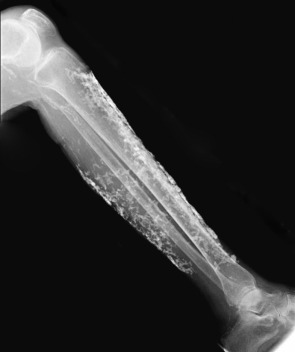

The most common cause of metastatic calcification is advanced chronic kidney disease ( Fig. 50.4 ). In patients with renal failure, there is an impaired ability to clear phosphate and impaired activation of vitamin D3, as 1-α hydroxylation occurs in the kidney. Impaired production of 1,25-dihydroxyvitamin D 3 leads to decreased absorption of calcium from the intestine and hypocalcemia. Hypocalcemia, in turn, induces increased secretion of parathyroid hormone (PTH) and subsequent mobilization of calcium and phosphate. The serum calcium concentration is normalized, but significant hyperphosphatemia may develop, and, if the solubility product of calcium × phosphate is exceeded, metastatic calcification can result.

Benign nodular calcification usually develops in the setting of prolonged secondary hyperparathyroidism due to advanced chronic kidney disease. Clinically, there are large deposits of calcium in the skin and subcutaneous tissue, often in periarticular sites. The number and size correlate with the severity of the hyperphosphatemia. The lesions are usually asymptomatic except for pain from pressure placed on surrounding structures. Normalization of serum calcium and phosphate levels may result in resorption of the lesions; however, if larger deposits interfere with function, surgical removal is recommended.